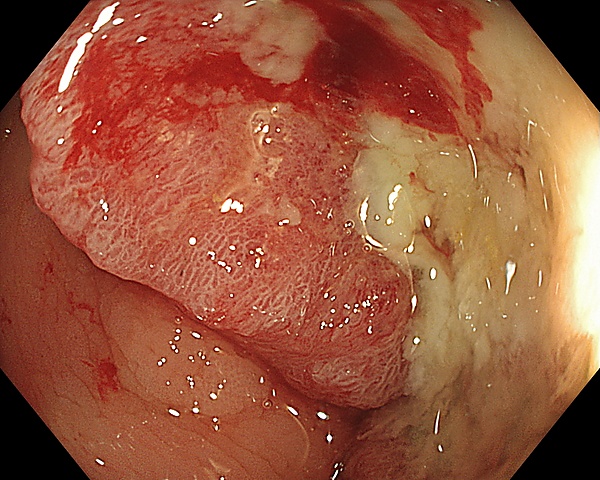

- колоноскопию;